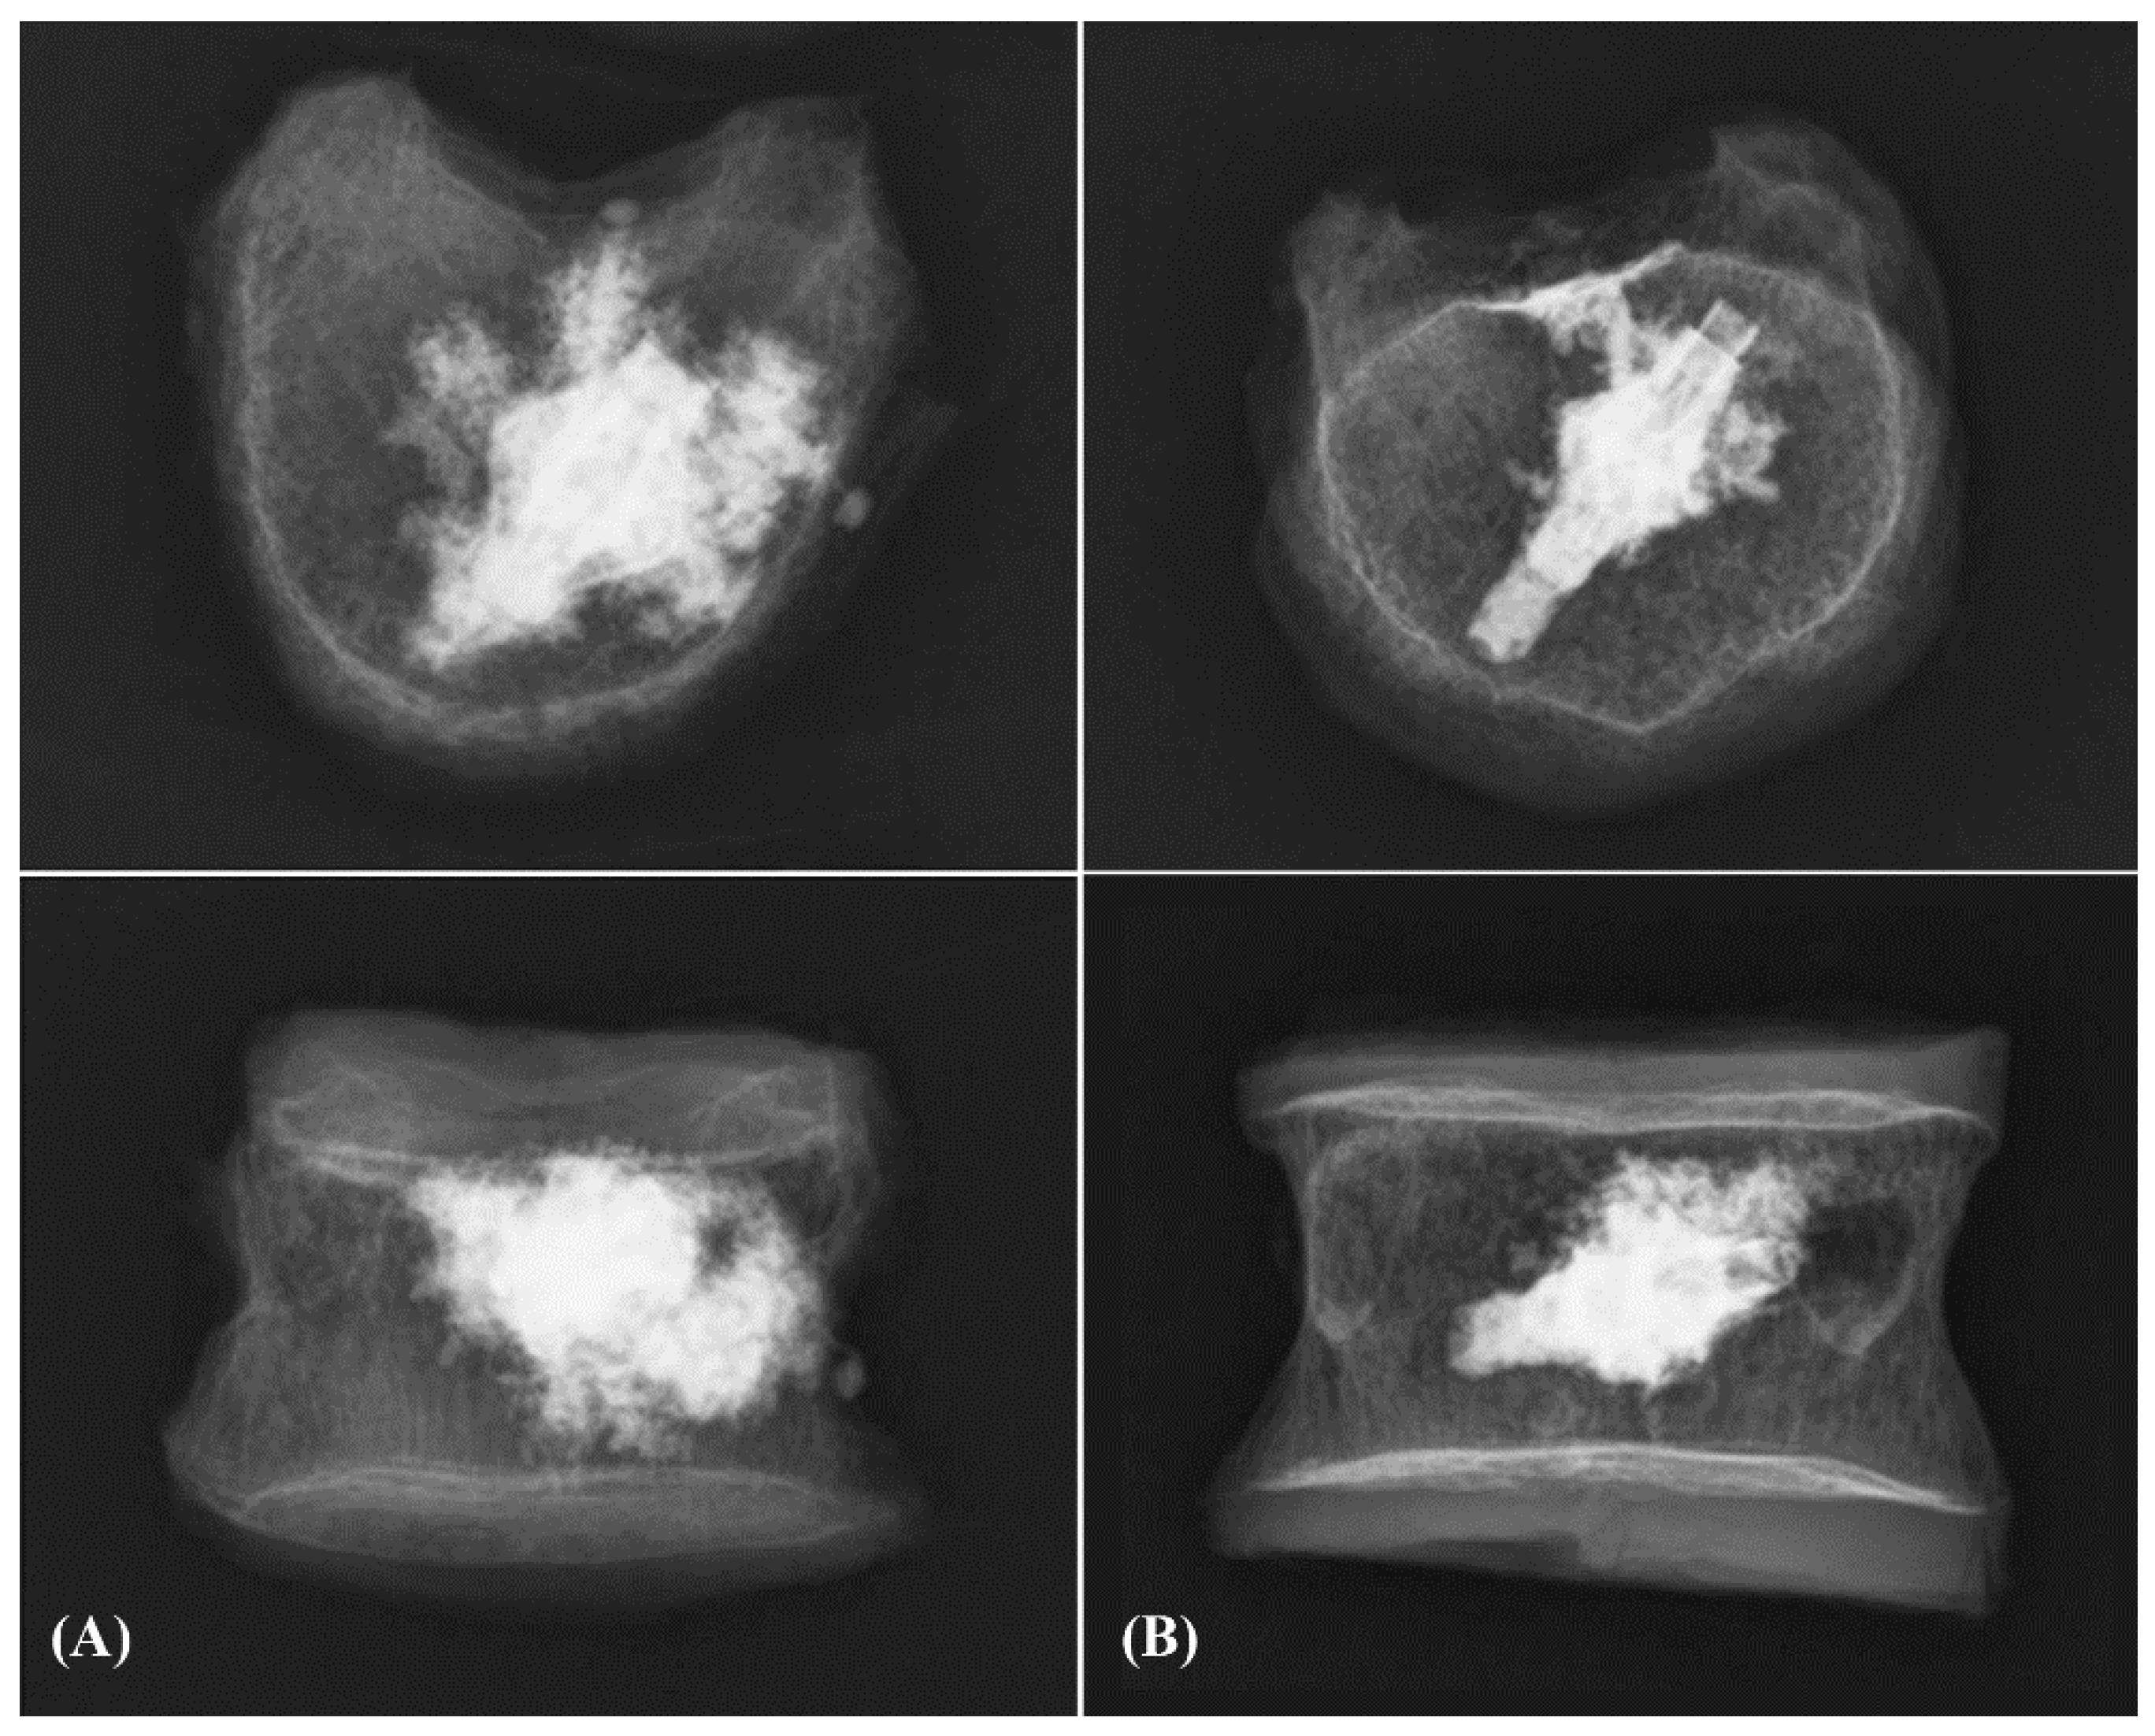

2.3. Implantation of EVA®

2.4. Implantation of OsseoFix®